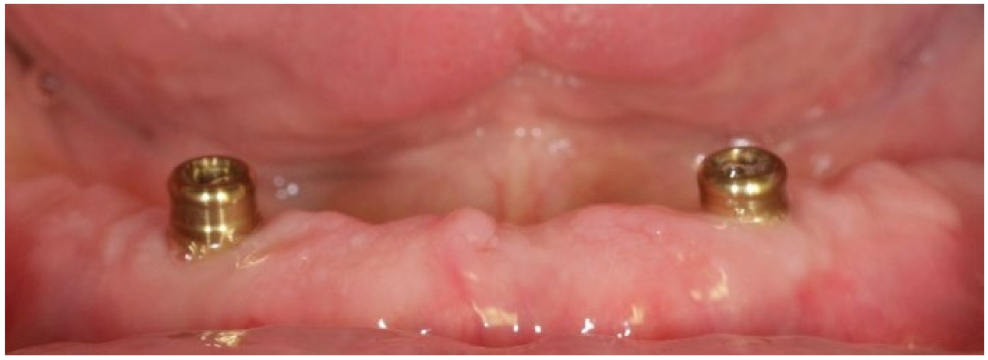

2. Materials and Methods

3. Results